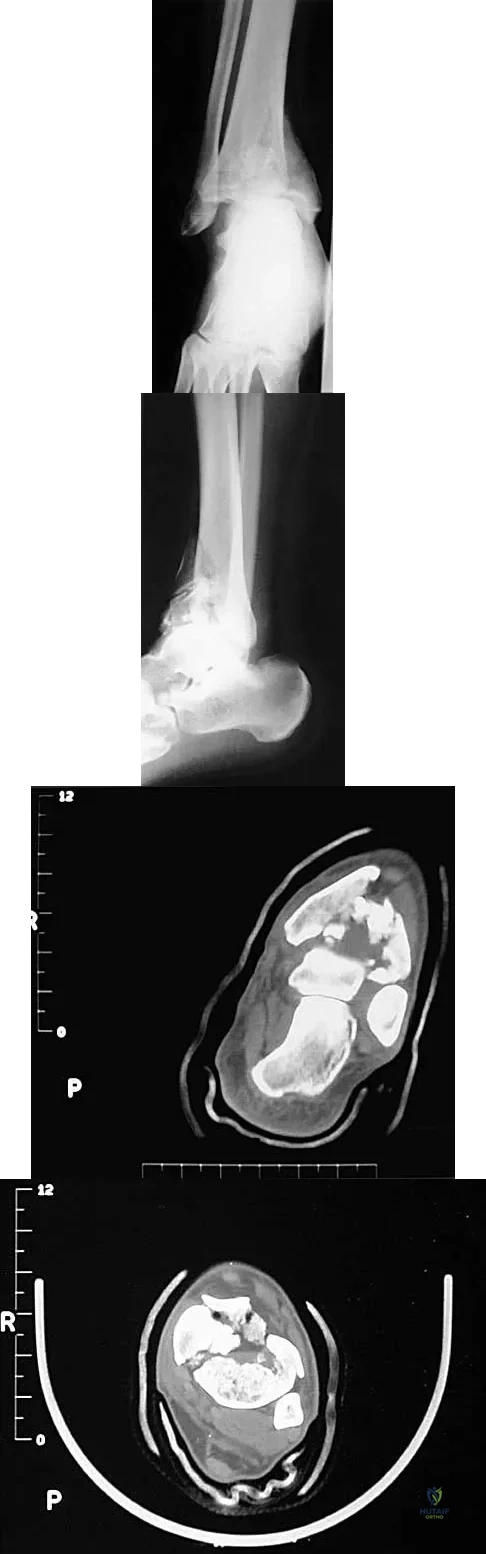

A 32-year-old man sustained a closed injury after falling 25 feet from a roof. His ankle and foot are severely swollen. Radiographs and CT scans are shown in Figures 29a through 29d. Initial management should consist of

Explanation